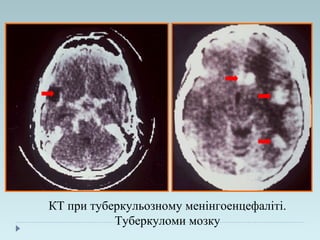

КТ при туберкульозному менінгоенцефаліті.

Туберкуломи мозку